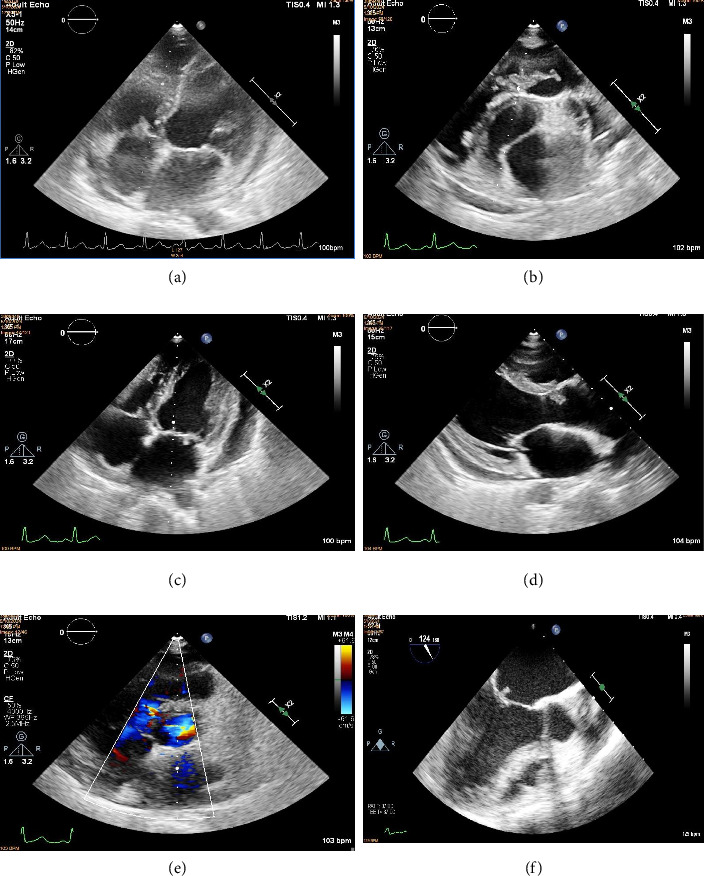

Infective endocarditis is a devastating disease with high morbidity and mortality. Infective endocarditis affecting all four valves is rarely encountered. Even rarer is the involvement of all four valves by nutritionally variant streptococci, Granulicatella. The case describes a female in her 40s, known case of small perimembranous ventricular septal defect, who presented with symptoms of fever and congestive cardiac failure, with severe anemia, glomerulonephritis, and pain abdomen, who was found to have vegetations on pulmonary, tricuspid, mitral, and aortic valves, with pulmonary regurgitation, tricuspid regurgitation, mitral, and aortic regurgitations. Blood culture grew Granulicatella adiacens species. She improved clinically after intravenous antibiotics, decongestive measures, and blood transfusion. Causation of quadrivalvular infective endocarditis is rare and previously has not been documented in Granulicatella infection, a fastidious species. Interestingly, the patient remained quite stable despite involvement of all four heart valves, likely due to the predominant involvement of the pulmonary valve. This case report discusses the factors predisposing to infective endocarditis in a known case of congenital heart disease and the importance of timely diagnosis and treatment.